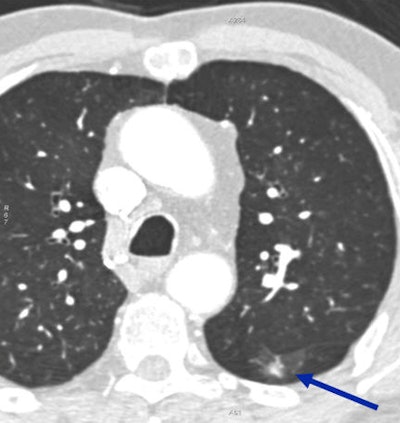

- Noteworthy but of minimal, if any, significance: small hiatal hernia, vascular anomaly, nodule smaller than 4 mm in a low-risk patient

- Chronic significance: nodules 4 mm and larger, lymphadenopathy

For example, a 2008 paper examined the issue and found that only a third of nodules visible on a full FOV reconstruction could be seen using a limited field-of-view.

Viewing cardiac CT scans obtained using only a limited field-of-view "can result in missing more than 67% of nodules larger than 1 cm and more than 80% of nodules smaller than 1 cm," wrote Dr. Meredith Northam and colleagues in the American Journal of Roentgenology in 2008.

Lung nodules are the principal finding that benefits from full FOV reconstructions, White noted, citing a 2010 study in the Journal of Computer Assisted Tomography. Dr. John Fantauzzi and colleagues found that a full FOV approach included 58% (range, 26% to 86%) of the lungs, versus just 14% (range, 8% to 22%) in a limited field-of-view, obviously offering far greater opportunities to detect nodules. But neither captures the entire lung region.